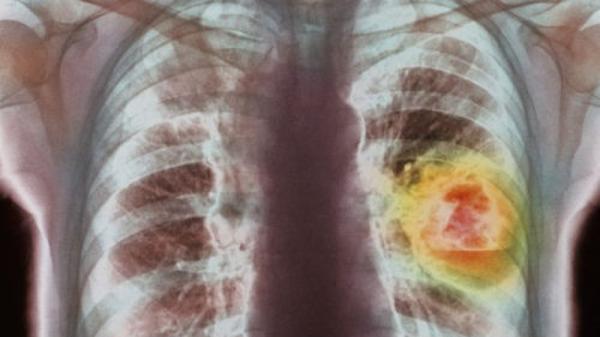

呼气就能测肺癌?英国将对新仪器进行临床试验

剑桥大学的一家分支公司“欧尔斯通”开发的这台“肺癌显示检测器”用于检查呼气中的化学物质,从而显示患者是否可能患有肺癌。

尽早诊断可以提高肺癌患者的存活率。

他希望有关科技可以尽早诊断出患者的肺癌情况。在英国每年有3万5千多人死于肺癌,存活率很低,原因是很多病例诊断出的时候已经属于末期癌症。